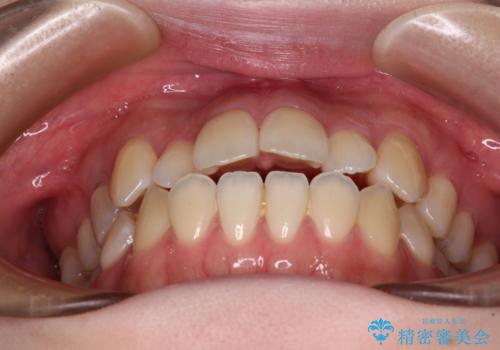

- 上下前歯の隙間を気にして来院された患者様です。

前歯が、舌の突出癖により上下前歯が非接触となっている状態でした。

ワイヤー矯正での開咬改善には時間がかかります。

舌の突出癖改善のトレーニングをしっかりと行っていただき、上下前歯が接触する咬み合わせを達成することができました。